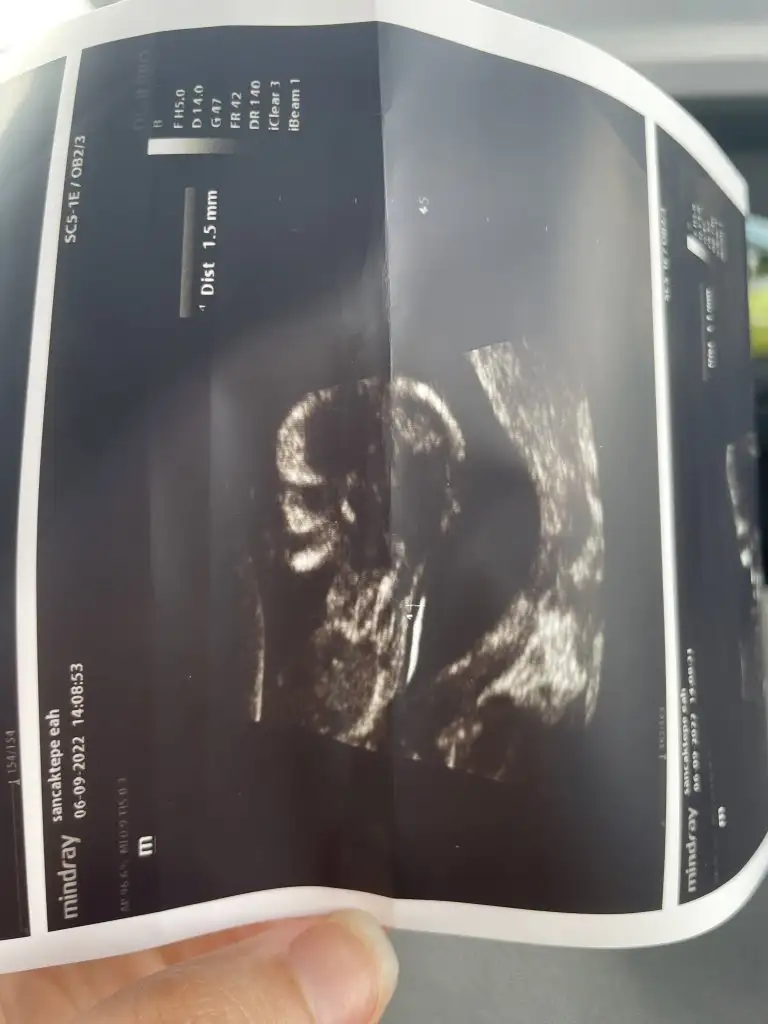

Canım kafa yapısı erkek gibi ama nub bolgesi hic gorunmuyor, sanırım yine bir sonraki kontrolü bekliycez senin icin

Haha yine mi gool degil diyesim geldiCanım kafa yapısı erkek gibi ama nub bolgesi hic gorunmuyor, sanırım yine bir sonraki kontrolü bekliycez senin icin

İkili odaklı olduğu için bu şekilultrason görüntüsü varmı :)